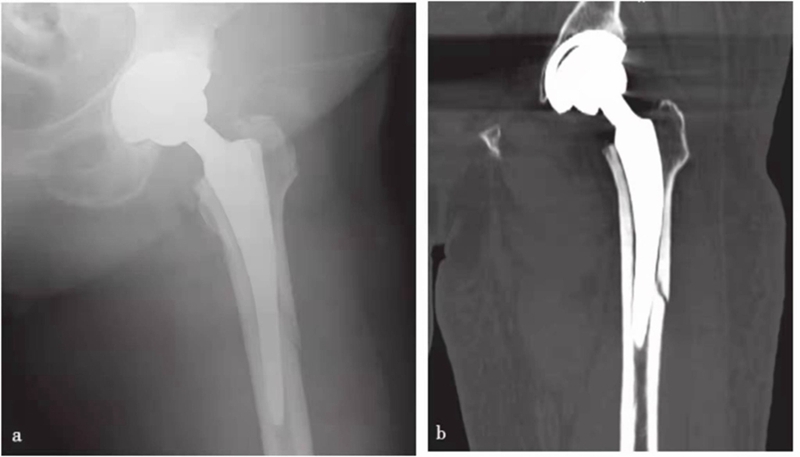

图14 人工关节置换术后股骨干骨折

平片,示左侧假体柄尖部附近股骨干骨折并错位

图15 人工关节置换术后股骨干骨折

a. X线片;b. CT冠状位重建,示左侧假体柄远端附近股骨干骨折